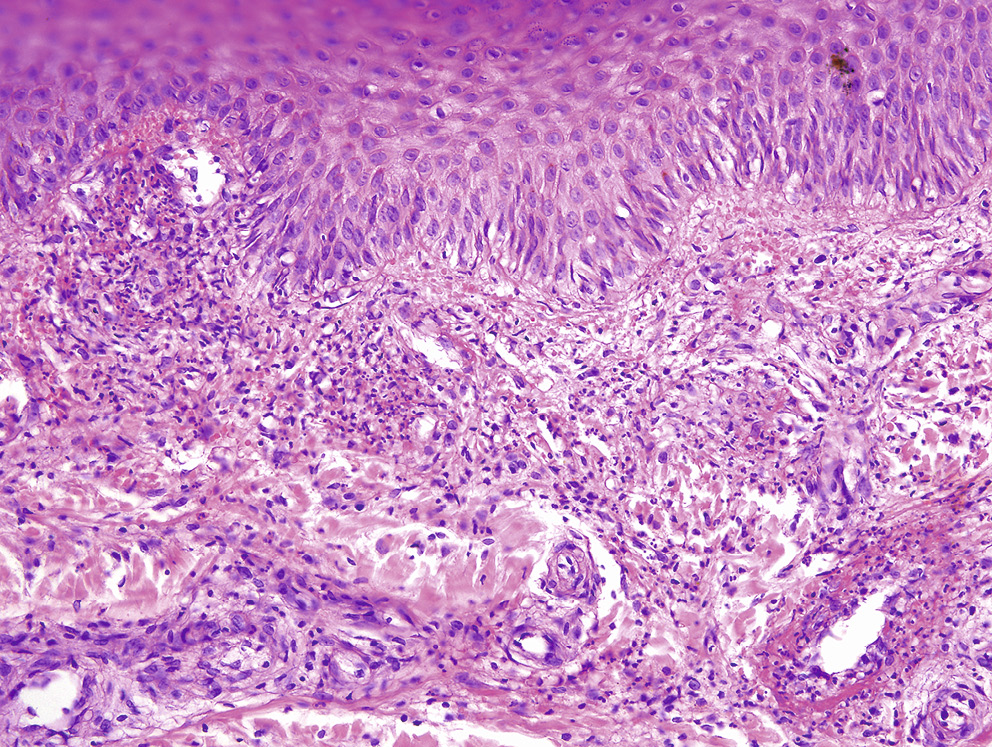

Нодулярный (узловатый) васкулит (индуративная эритема Базена) представляет лобулярный панникулит с васкулитом сосудов гиподермы. Наиболее часто выявляется поражение венул жировых долек, реже — малых лобулярных и септальных вен, еще реже — изолированное поражение малых вен и артерий септальных перегородок подкожной клетчатки (рис. 3, 4). Кроме васкулита, патоморфологические изменения кожи могут включать коагуляционный и казеозный некроз, а также нейтрофильные, гранулематозные или лимфоцитарные инфильтраты. При дифференциальной диагностике с острой узловатой эритемой учитывают, что для нодулярного васкулита характерно хроническое течение, поражение сгибательных поверхностей голеней, изъязвление узлов, при гистологическом исследовании выявляется поражение долек гиподермы. Узловатая эритема имеет острое течение, узлы локализуются на переднебоковых поверхностях голеней, не изъязвляются, патоморфологические изменения представлены септальным панникулитом без васкулита [30].

Рис. 3. Нодулярный (узловатый) васкулит. Поражение септальной артерии подкожной клетчатки (септальный васкулит). Инфильтрация нейтрофильными лейкоцитами мышечного слоя, отек и пролиферация эндотелиальных клеток

Fig. 3. Nodular (erythema induratum) vasculitis. Lesions of the septal artery of the hypoderm (septal vasculitis). Muscular layer neutrophilic leukocyte infiltration, edema and proliferation of endothelial cells

Рис. 4. Нодулярный (узловатый) васкулит. Поражение венул жировых долек (лобулярный васкулит). Некроз и инфильтрация нейтрофильными лейкоцитами стенок вен с явлениями тромбоза

Fig. 4. Nodular (erythema induratum) vasculitis. Lesions of venules of fatty lobules (lobular vasculitis). Necrosis and neutrophilic leukocyte infiltration of vein walls with thrombosis